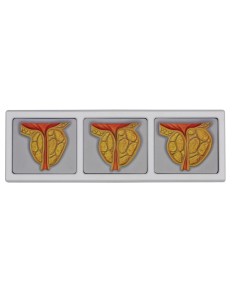

Scopri il Mondo dell’Anatomia con Modelli anatomici di Precisione

Modelli Anatomici Dettagliati per Ogni Necessità

Strumenti Didattici Innovativi per l’Educazione e la Pratica Medica

Essenziali per studenti e professionisti, i nostri modelli anatomici sono strumenti didattici che permettono di osservare le strutture anatomiche con precisione, eliminando la necessità di dissezioni o studi invasivi. Sono inoltre utili per spiegare ai pazienti le patologie, rendendo la comunicazione più efficace e risparmiando tempo prezioso.